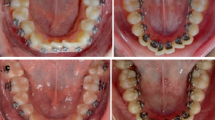

All of the teeth were sand blasted with aluminum oxide (50 µm), then etched for 30 s with 32% orthophosphoric acid (Scotchbond, 3M Unitek, Monrovia, CA, USA), rinsed with water for 30 s, and dried for 20 s. Test brackets (Customized Incognito lingual brackets slot size 0.018″ × 0.025″) were indirectly bonded using the provided tray with an orthodontic composite (RelyX Unicem 2 Automix; 3M Unitek). After the composite was cured, all samples were extracted from the resin block and tied to the Incognito 0.018″ × 0.025″ stainless steel (SS) arch wire one by one. The tooth crowns were then included in a block of soft wax to remain stable in relation to each other. Once more, the lateral surface of the resin block was dug out with a denture bur contained in a straight handpiece, and the tooth roots were placed in a straight line in the pit and encased in transparent fluid resin (methyl methacrylate). The resin was cured, and the wax was removed from the crowns. The resulting teeth position in the idealized cast allowed slots to be passively engaged by the arch wire (Fig. 1a).

a Custom-made idealized cast; b bonded lingual brackets with a wire; c idealized cast fixed to the machine; d experimental setting; e enarthrosis connection between the screw and the machine; f perforated screw